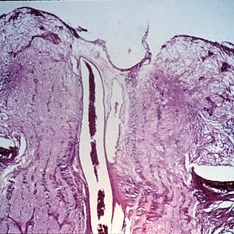

Slide 11-10

Feb 26 2019 by Lancaster Course in Ophthalmology

Papilledema. Enlargement of the nerve sheath (X 16).

Condition/keywords: papilledema